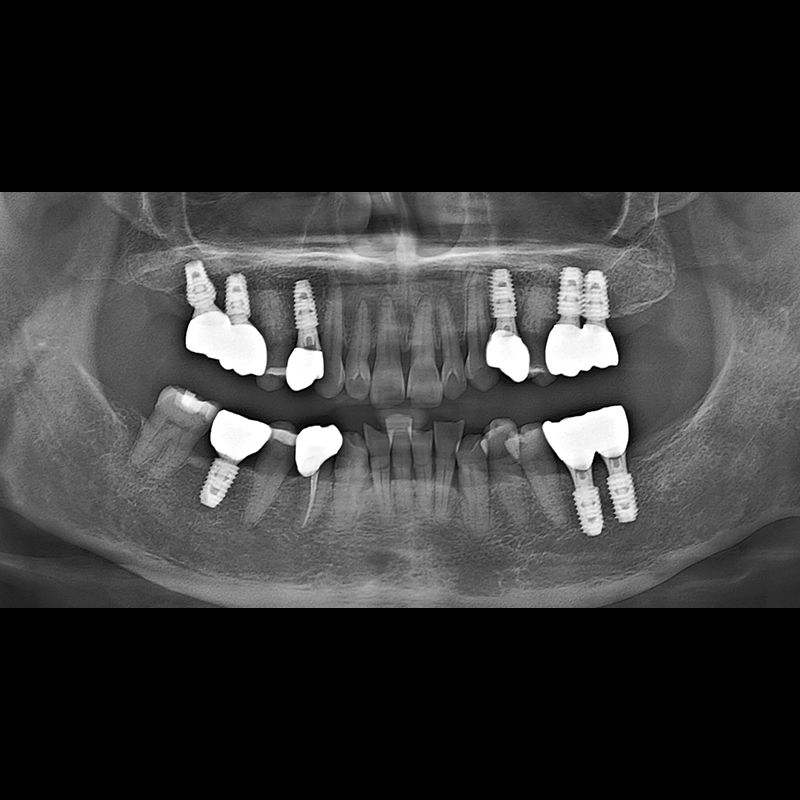

IMPLANT

BEFORE AFTER

インプラント手術事例 2025.05.30

欠損した歯の部分と、生かしにくい歯の位置にインプラントを植立しました。